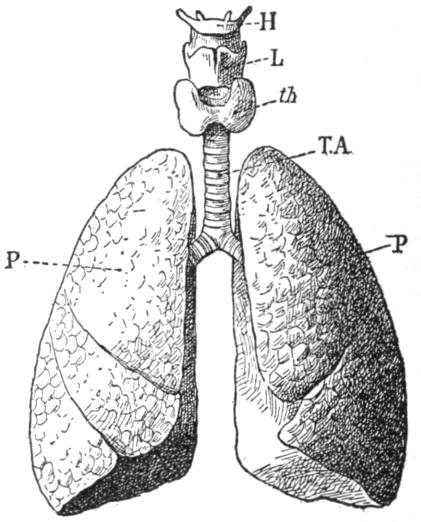

| VI. | The Respiration | H 70 |